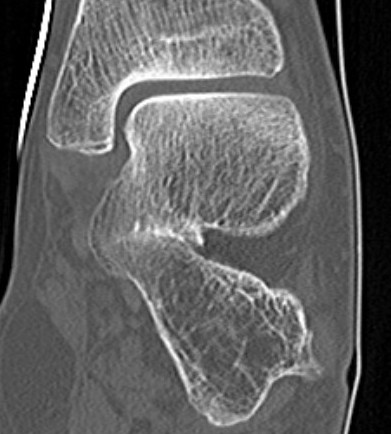

CT

TC coalition middle facet

Complete synostosis of the medial TC joint with OA of the posterior subtalar joint